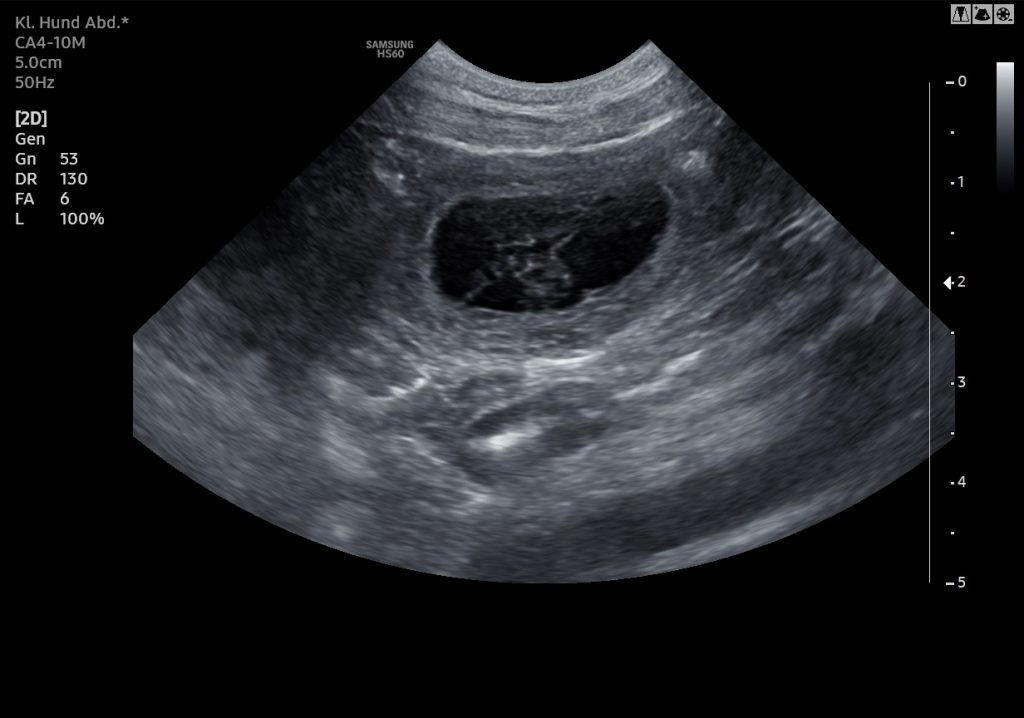

Der Ultraschall hat es bestätigt: Hedda vom Landgöding ist tragend – es sind mindestens 6 Fruchtanlagen zu erkennen. Juhu!

Die kleinen Herzen schlagen bereits und wir freuen uns sehr auf das, was nun vor uns liegt.